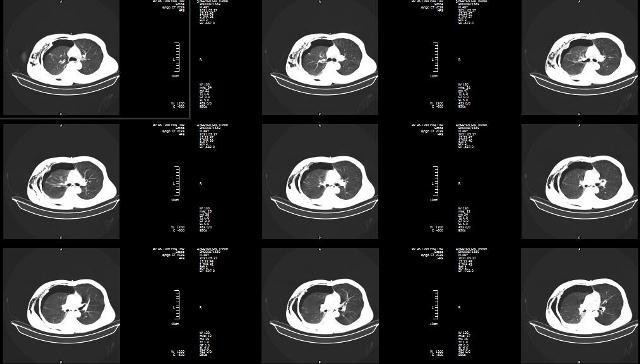

Người bệnh được đặt ống nội khí quản, sơ cứu ban đầu và được chỉ định chụp chiếu. Kết quả chụp cho thấy người bệnh bị gãy toàn bộ xương sườn ở bên phải gây tràn dịch, tràn khí màng phổi, tràn khí trung thất, đụng dập nhu mô phổi. Các chuyên khoa đã nhanh chóng hội chẩn và người bệnh được chỉ định cấp cứu: Mở màng phổi, dẫn lưu khí máy màng phổi và tạo mỏm cụt tay phải.

![]() |